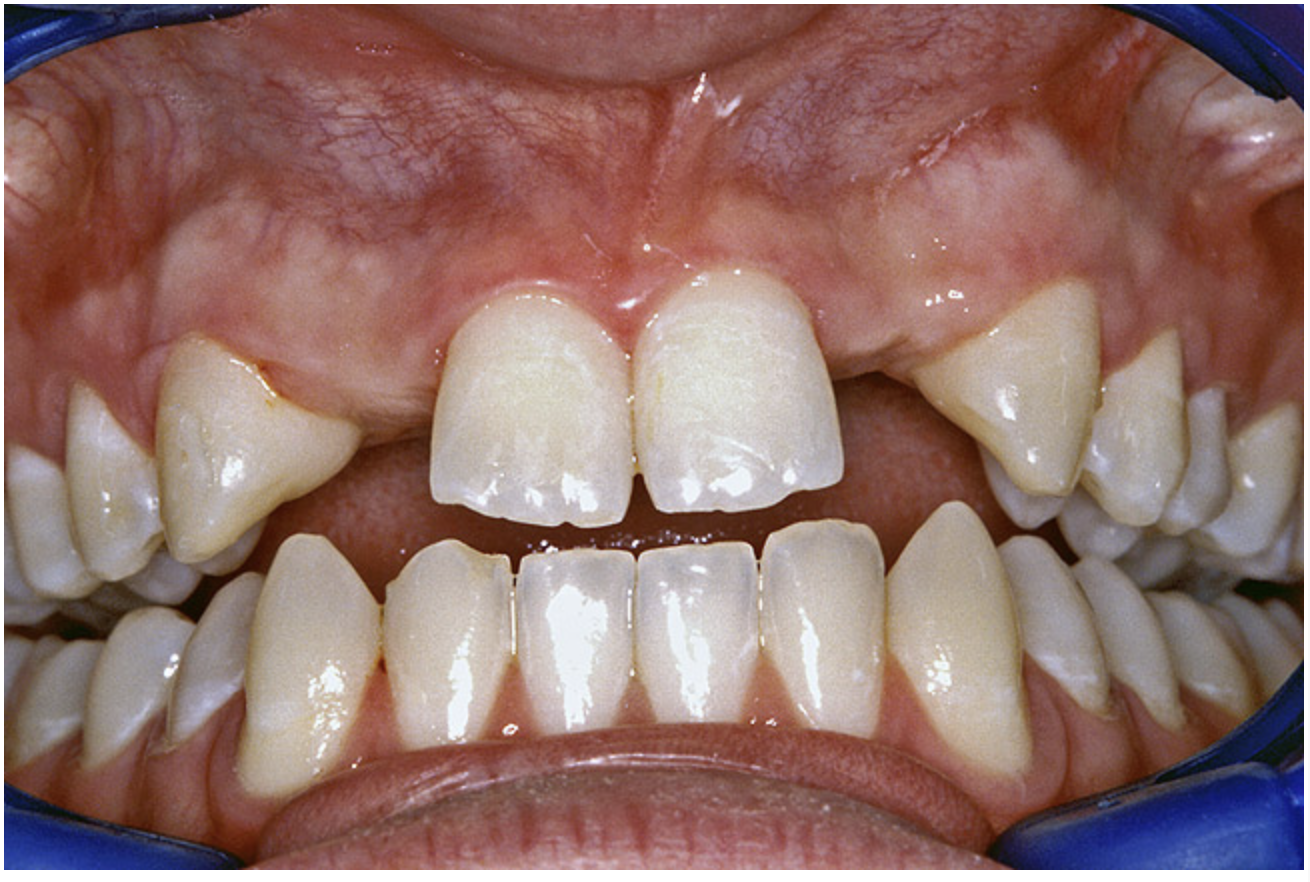

Periapical radiographs were taken to help determine the mesial-distal inclinations of the adjacent tooth roots (Figure 1). The radiographs revealed a serious issue, convergent roots for the right canine and right central, which eliminated that area as a potential implant-receptor site. The space between the left central and canine teeth was minimal, although the roots were relatively parallel. Clinical examination (manual palpation of the root eminences superiorly to the vestibule on the right side) confirmed the root convergence (Figure 2A). The flat, wide zone of the keratinized tissue and lack of interdental papilla was evident for the missing right lateral incisor. There was a marked difference in clinical appearance for the left lateral, which could impact the eventual plan of treatment (Figure 2B). Other significant clinical findings included bilateral facial bone concavities, which existed as a result of the congenitally missing tooth roots. As a diagnostic cue to the underlying bone topography, it is important to follow the demarcation between attached and unattached gingival tissue, and note the crestal width of the available keratinized tissue (Figure 2C).

Figure 2a  Pretreatment buccal views showed (A) root convergence, (B) a difference in clinical appearance of the left lateral, and (C) significant crestal width of keratinized tissue.

Figure 2b  Pretreatment buccal views showed (A) root convergence, (B) a difference in clinical appearance of the left lateral, and (C) significant crestal width of keratinized tissue.

Figure 2c  Pretreatment buccal views showed (A) root convergence, (B) a difference in clinical appearance of the left lateral, and (C) significant crestal width of keratinized tissue.